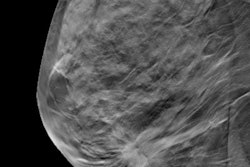

Volumetric percent density from DBT images was compared to both calculations of breast density using volume- and area-based methods based on digital mammography images acquired from publicly and commercially available software, including the Laboratory for Individualized Breast Radiodensity Assessment (LIBRA), the Quantra software from Hologic, and the Volpara software from Volpara Health.

The researchers found that DBT-based density calculations had the highest association with breast cancer risk, with each standard deviation of volumetric breast density representing a twofold higher cancer risk, as measured by odds ratio.

While area under the curve (AUC) for the measures were close to each other, with the lowest being 0.58, volume-based percent density for DBT images had the highest AUC at 0.62.

The researchers said the study showed "only moderate" correlations between DBT and DM density measures, which also varied with density and breast thickness categories.